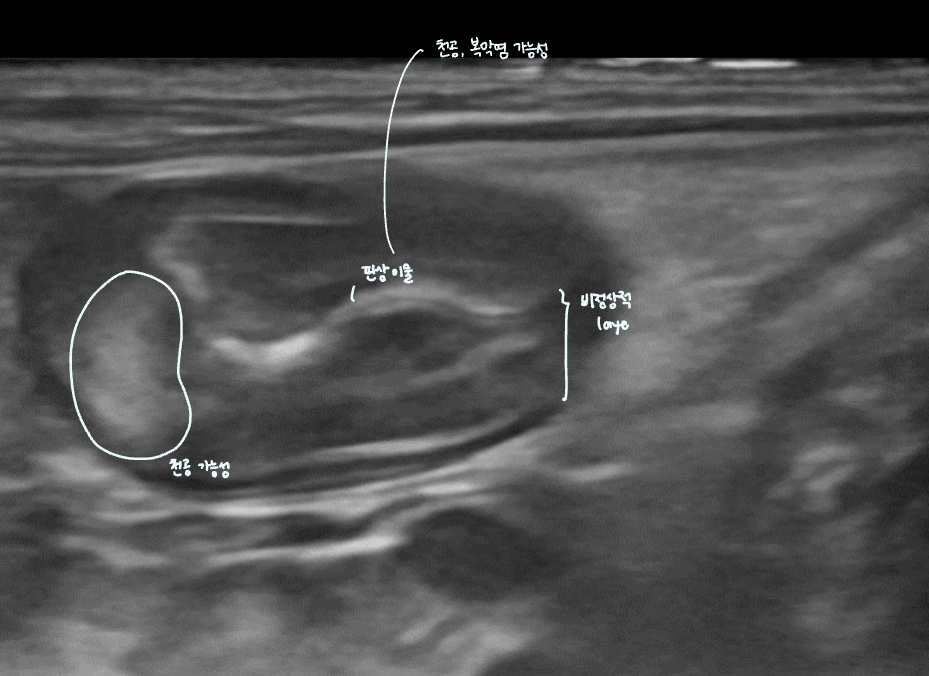

์ ์ ๊ตฌ์กฐ ๊ด์ฐฐ

โ ์ฅ์ ๋จ๋ฉด (๋ฒฝ ๊ตฌ์กฐ ๊ตฌ๋ถ)

- ์์ชฝ๋ฉด๋ถํฐ 4์ธต์ ๊ตฌ์กฐ๋ก ์ด๋ฃจ์ด์ง.

- ์ ๋ง์ธต | Mucosa (์ ์์ฝ์ฑ, ์ด๋์)

- ์ ๋งํ์ธต | Submucosa (๊ณ ์์ฝ์ฑ, ๋ฐ์) โ ๊ฒฐํฉ์กฐ์ง, ๋ฐ์ฌ๊ฐ ๊ฐํด hyperechoic

- ๊ทผ์ก์ธต | Muscularis (์ ์์ฝ์ฑ,์ด๋์)

- ์ฅ๋ง์ธต | Serosa (๊ณ ์์ฝ์ฑ, ๋ฐ์) โ ๊ฒฐํฉ์กฐ์ง, ๋ฐ์ฌ๊ฐ ๊ฐํด hyperechoic

(๋์นญ ๊ตฌ์กฐ์ ์ค์ฌ์ด ๋๋ ํฐ์ ๋ด๊ฐ์ ์ฐพ๋๋ค. ๋ด๊ฐ์์๋ถํฐ ๊ฒ-ํฐ-๊ฒ-ํฐ 4์ธต ๊ตฌ์กฐ๋ฅผ ํ์ธํ ์ ์๋ค.)

์์ํ์ ์๊ฒฌ : ๋นํ๋ ์๋ฒฝ(2๋ฐฐ ์ด์์ด๋ฉด ์์ฌ), filling defect(์กฐ์ ์ดฌ์)

- ์์ฌ๋๋ค๋ฉด โ ์ด์ํ๋ก ์๋ฒฝ ํ์ธ!

- Wall pseudolayering : adenocarcinoma์ ๊ฐ์ฅ ํฐ ํน์ง

- ์๋ฒฝ์ด ๋นํ๋์ด, layer๊ฐ ์๋๋ฐ layer์ฒ๋ผ ๋ณด์ โ ์๋ฒฝ์ ์๋ 4๊ฐ ์ธต์ธ๋ฐ, ๋ ์ฌ๋ฌ ์ธต์ผ๋ก ๋ณด์.